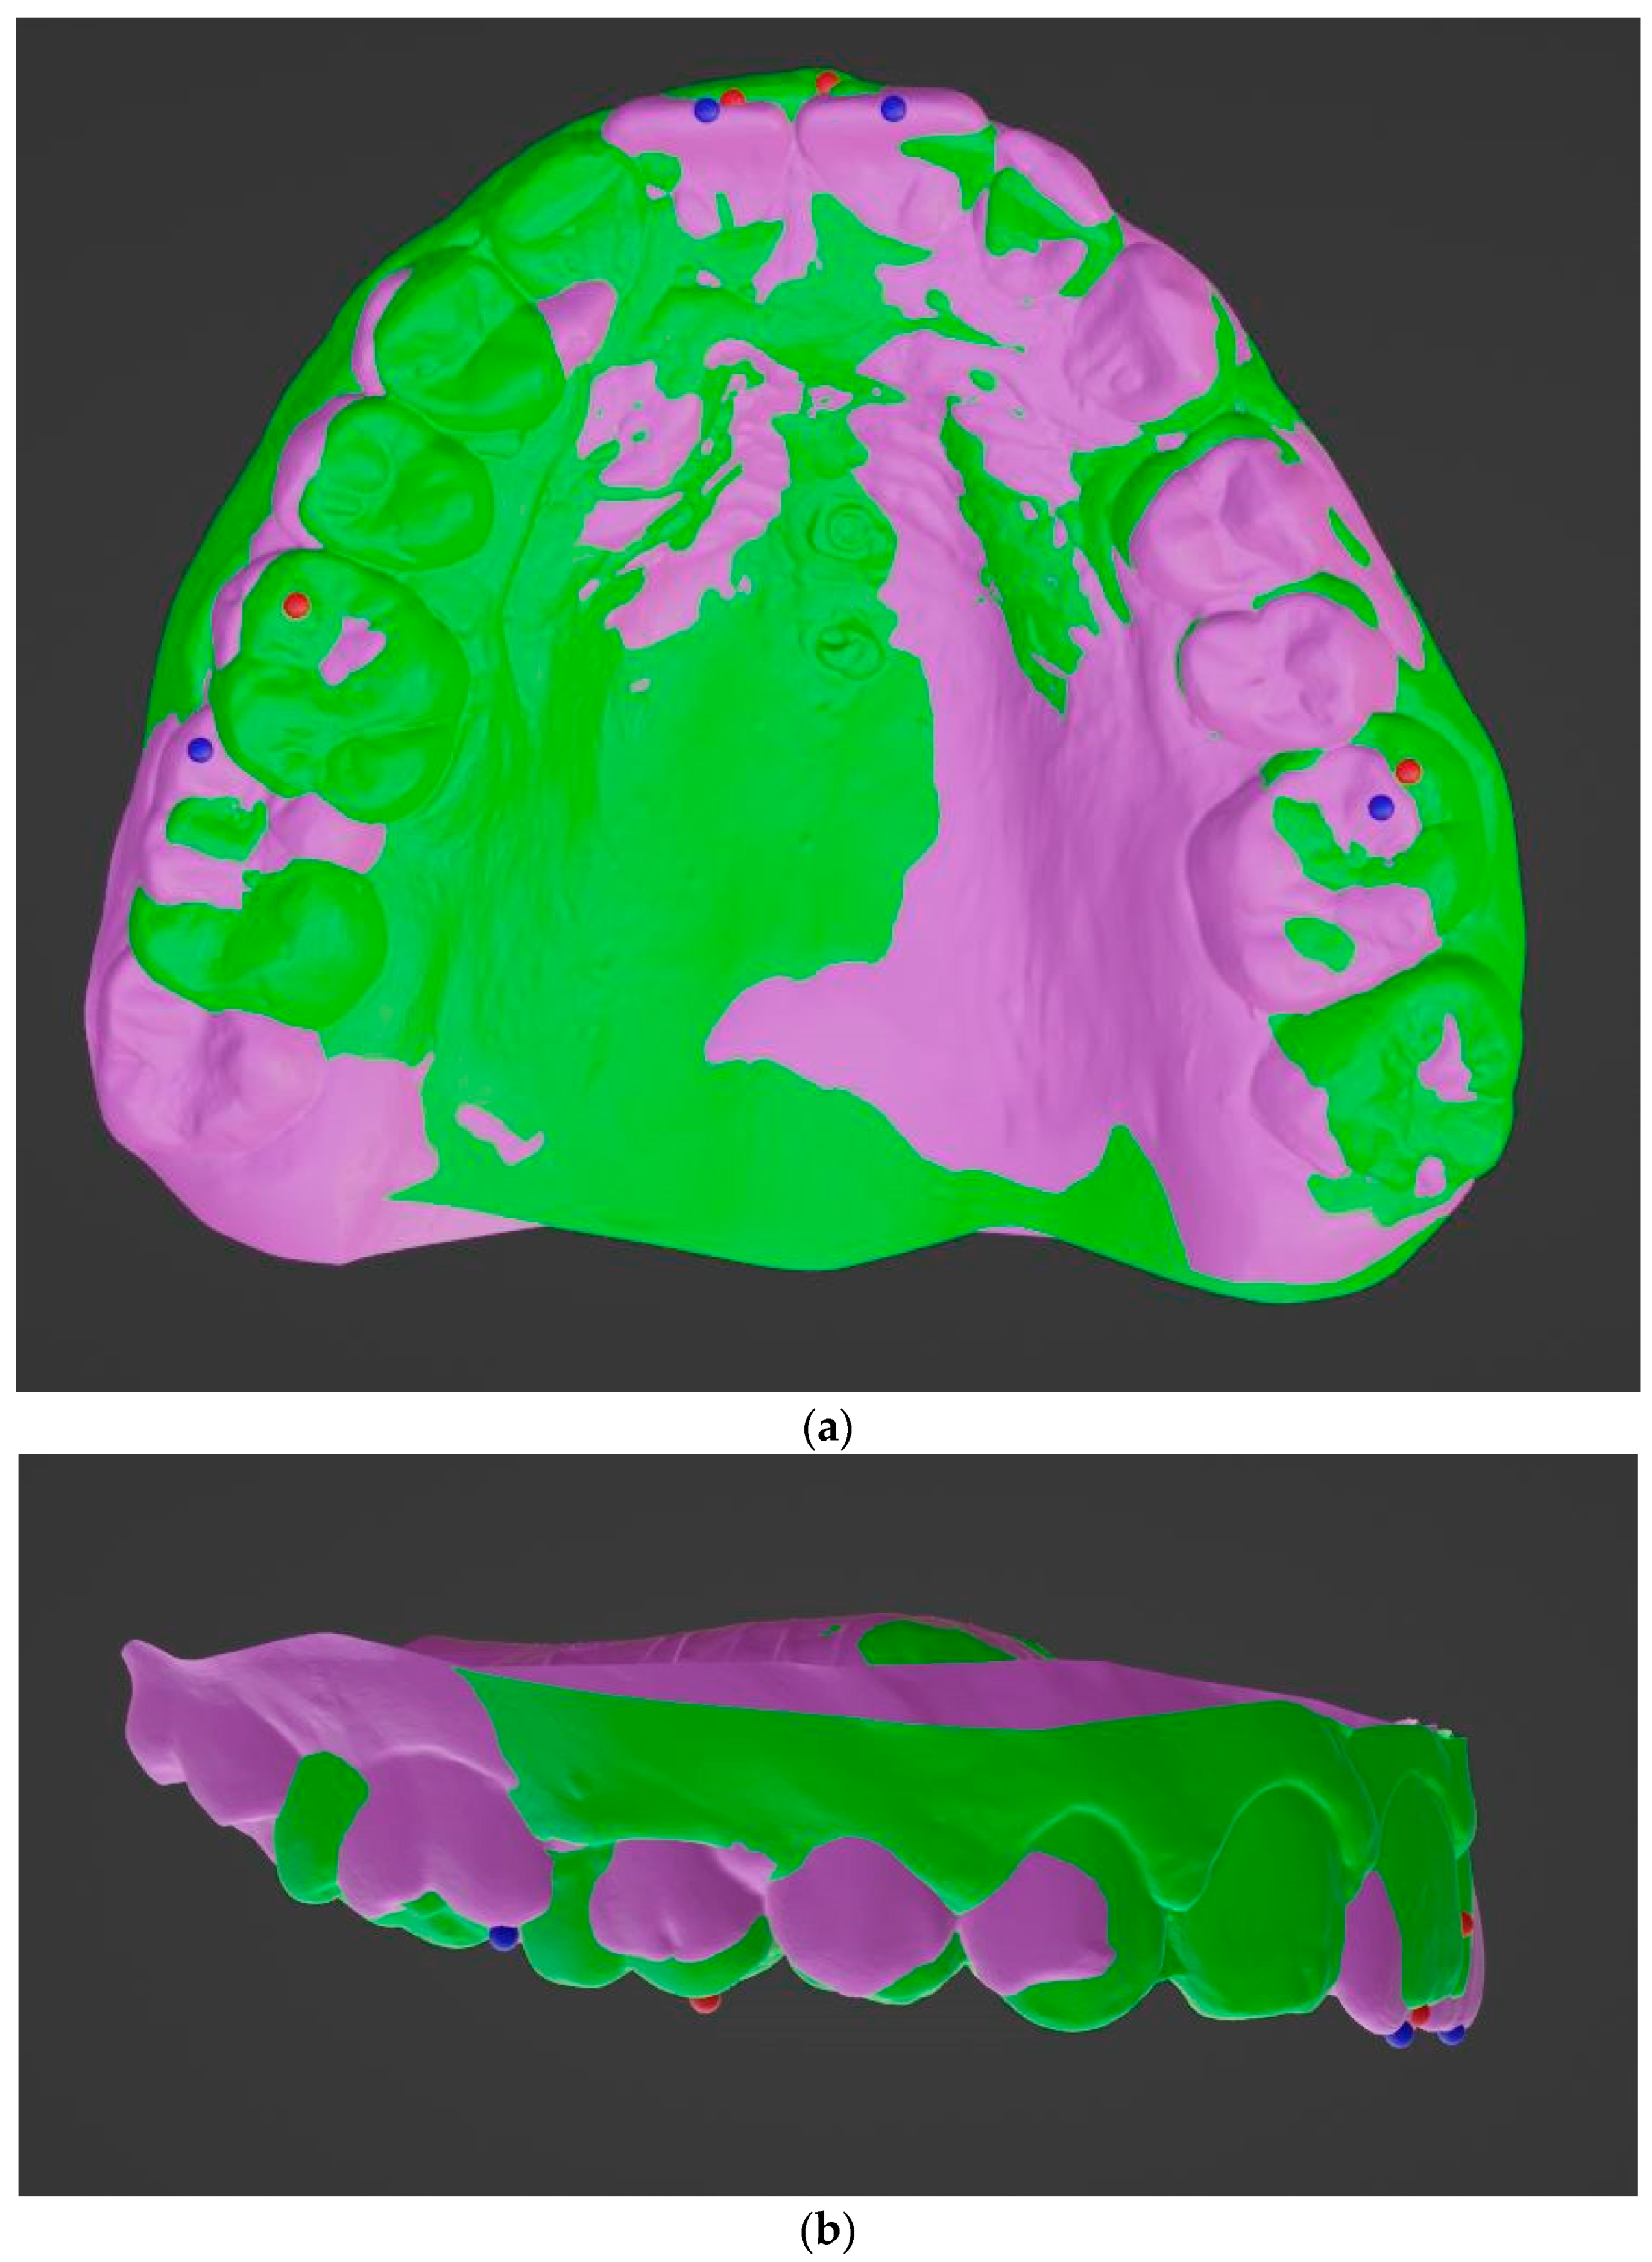

- Becker, K.; Wilmes, B.; Grandjean, C.; Drescher, D. Impact of manual control point selection accuracy on automated surface matching of digital dental models. Clin. Oral. Investig. 2018, 22, 801–810. [Google Scholar] [CrossRef]

- Almeida, M.A.; Phillips, C.; Kula, K.; Tulloch, C. Stability of the palatal rugae as landmarks for analysis of dental casts. Angle Orthod. 1995, 65, 43–48. [Google Scholar]

- Hoggan, B.R.; Sadowsky, C. The use of palatal rugae for the assessment of anteroposterior tooth movements. Am. J. Orthod. Dentofac. Orthop. 2001, 119, 482–488. [Google Scholar] [CrossRef]

- Kim, H.K.; Moon, S.C.; Lee, S.J.; Park, Y.S. Three-dimensional biometric study of palatine rugae in children with a mixed-model analysis: A 9-year longitudinal study. Am. J. Orthod. Dentofac. Orthop. 2012, 141, 590–597. [Google Scholar] [CrossRef] [PubMed]

- Choi, D.S.; Jeong, Y.M.; Jang, I.; Jost-Brinkmann, P.G.; Cha, B.K. Accuracy and reliability of palatal superimposition of three-dimensional digital models. Angle Orthod. 2010, 80, 497–503. [Google Scholar] [CrossRef] [PubMed]

- Choi, J.I.; Cha, B.K.; Jost-Brinkmann, P.G.; Choi, D.S.; Jang, I.S. Validity of palatal superimposition of 3-dimensional digital models in cases treated with rapid maxillary expansion and maxillary protraction headgear. Korean J. Orthod. 2012, 42, 235–241. [Google Scholar] [CrossRef]